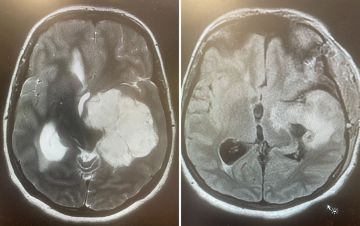

أعلن الفريق الطبي المتخصص في جراحة المخ والأعصاب بمستشفى الملك عبدالعزيز التخصصي، التابع لتجمُّع الطائف الصحي، نجاح عملية جراحية دقيقة ونادرة، أُجريت لشابة تبلغ من العمر 29 عامًا، تمثلت في استئصال ورم دماغي كبير ومستقر في الفص الصدغي الأيسر، ممتدًّا إلى قاعدة الجمجمة وجذع الدماغ.

وتسبب هذا الورم للمريضة في ضعف حركي تشنجي في الجهة اليمنى من الجسم، إلى جانب اضطراب في التوازن، واختلال في النطق والذاكرة.

وجرى تنفيذ العملية بتقنية مجهرية عالية الدقة عبر تداخُل جناحي صدغي موسع؛ ما أتاح للفريق الطبي استكشاف الشرايين الدماغية والأعصاب القحفية المهمة للحياة، وفصلها بعناية عن كتلة الورم؛ بهدف الحفاظ على سلامتها.

واستمرت الجراحة عشر ساعات متواصلة، نجح خلالها الفريق في إزالة الورم بالكامل دون المساس بالمراكز الحيوية والوظائف الأساسية.

وبفضل الله تحسنت حالة المريضة بشكل ملحوظ منذ الساعات الأولى بعد العمل الجراحي، واستعادت قوتها العضلية والعقلية بصورة كاملة خلال ثلاثة أيام من إجراء العملية، وتمكنت من مغادرة المستشفى في اليوم الخامس وهي بكامل نشاطها الذهني والبدني، مع تحديد موعد متابعة لاحق؛ للاطمئنان على استقرار حالتها الصحية.